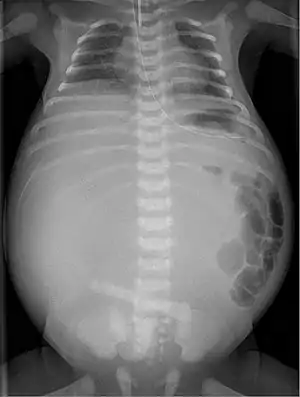

Complication of ileal atresia, meconium peritonitis, in which the bowel perforated before birth. X-ray shows meconium pseudocyst.

If the atresia is not treated, the bowel may become perforated or ischemic. This can lead to abdominal tenderness and meconium peritonitis, which can be fatal.[1]